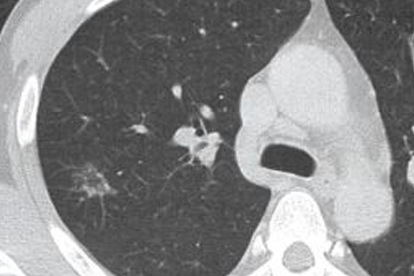

金黄色葡萄球菌肺炎常见于流感后继发感染,特征为坏死性肺炎伴血性脓痰。甲氧西林敏感菌株可用苯唑西林钠胶囊,耐药菌株需使用万古霉素注射剂或利奈唑胺片。该菌易形成肺脓肿,需配合影像学检查评估病情。

肺炎克雷伯菌多见于酒精中毒或糖尿病患者,典型症状包括砖红色胶冻样痰。第三代头孢菌素如头孢曲松钠注射剂是首选药物,产超广谱β-内酰胺酶菌株需使用亚胺培南西司他丁钠注射剂。该菌感染易进展为肺组织坏死。